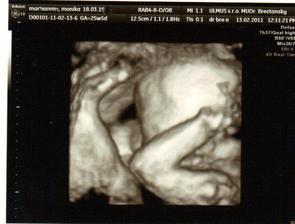

krasne 3D sono 🙂

Krasne foto dufam ze ti uz je lepsie mojko 🙂